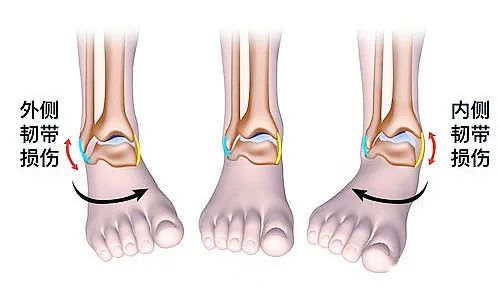

踝关节是负重比较大的关节,也是活动比较大的关节。踝关节骨折可能是由各种各样的外力造成的不同类型的损伤(如:外翻、内翻、外展、内旋等等)。对于医生来讲,每一种不同的受伤机制,他的治疗方案跟手术方案都是不一样的。

踝关节周围的韧带比较多(如:下跟距韧带、下胫腓联合韧带、三角韧带等等),伴随踝关节骨折的发生,这些韧带也常会出现不同程度的损伤。关节损伤加上韧带损伤,治疗起来就非常有难度。